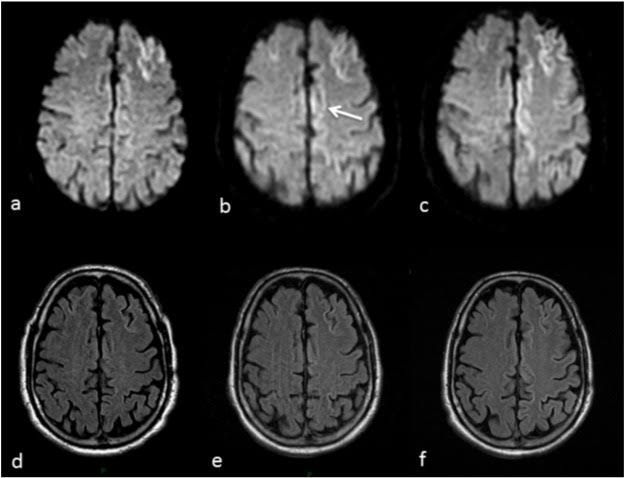

Creutzfeldt-Jakob (KROITS-felt YAH-kobe) disease (CJD) is a degenerative brain disorder that leads to dementia and, ultimately, death. Creutzfeldt-Jakob disease symptoms can be similar to those of other dementia-like brain disorders, such as Alzheimer's disease.